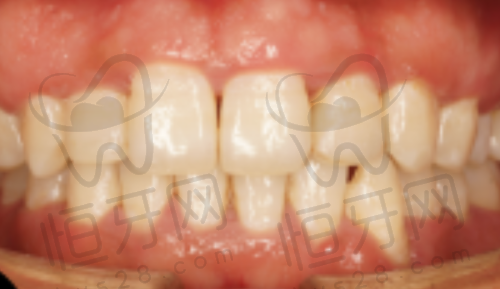

福州瑞尔口腔医院是国内连锁品牌,环境高端,正畸方案个性化程度高。

特色亮点:高端的环境能让患者在舒适的氛围中接受治疗,个性化的正畸方案则能根据每个患者的牙齿情况制定更适合的矫正方案。